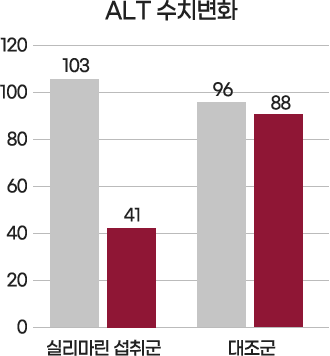

기능성 원료 ‘밀크씨슬추출물’ 인체시험 결과

2

섭취 전

섭취 8주 후

간세포 손상 정도를 나타내는 주요 지표인

ALT(103▶41)와 AST(53▶29)의 수치 개선 확인

[Study Design]

1) Silymarin 140mg/day 2) 대상자: 50명 섭취군 25명 대조군 25명 3) Placebo 2달 섭취 후 혈중 ALT, AST 측정함

*인체시험결과가 모든 사람에게 동일하게 적용되는 것은 아님 Ref. Hepatitis Monthly, 2008;8(3): 191-195